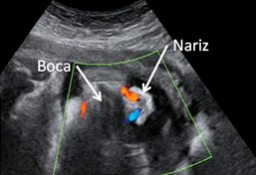

En la ecografía del tercer trimestre es muy difícil extraer una imagen completa del bebé. Rara vez se las apaña el ecografista para poder captar una "foto panorámica" de una criatura, que ya ocupa casi la totalidad del útero materno. Por eso, la mayoría de las ecos de esta edad gestacional se especializan en partes u órganos específicos del feto. El ecografista puede detectar aún ciertas anomalías del desarrollo, comprueba el líquido amniótico, el bienestar fetal y, muy importante, visualiza el cordón umbilical, que puede estar enrollado en algún órgano como cuello, pies o manos.